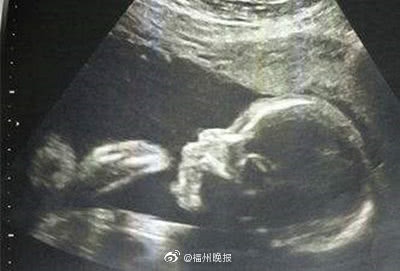

【超声排查变形胎儿 首选二维,不要迷信四维】临床上,产前超声技能包含二维、三维、四维技能。浅显来说,三者的区别是:二维是平面相片,三维是立体相片,四维则是会动的立体相片。关于孕妈做产检,医师主张在妊娠22周至26周时,做二维超声的大排畸查看,扫除心脏变形及其他变形。假如二维超声发现胎儿有反常,可再运用三维、四维探头扫查。